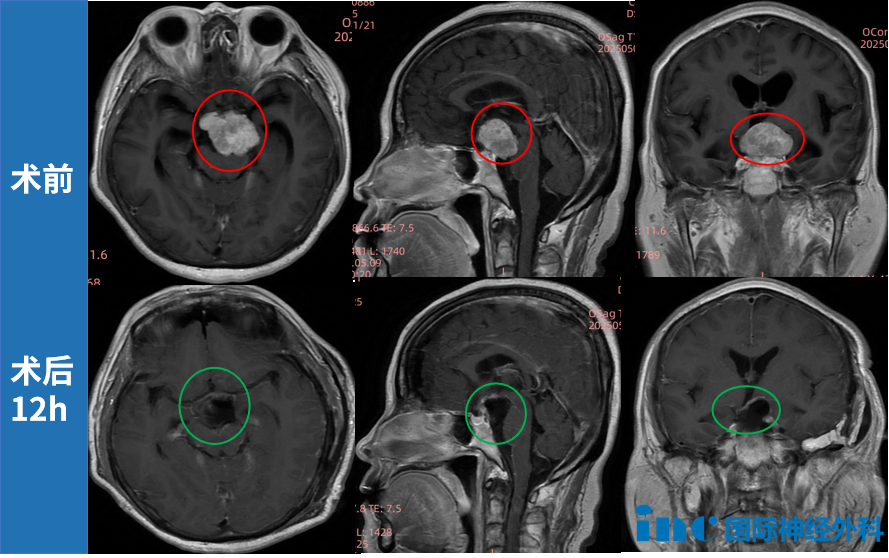

面对复杂手术挑战,INC教授术中借助"显微镜+神经内镜"双镜联合技术,在完好保留听力、面神经等重要功能前提下,成功实现肿瘤精准切除。术后病理提示II级,因切除满意,教授随访中建议无需放疗,仅需定期复查。